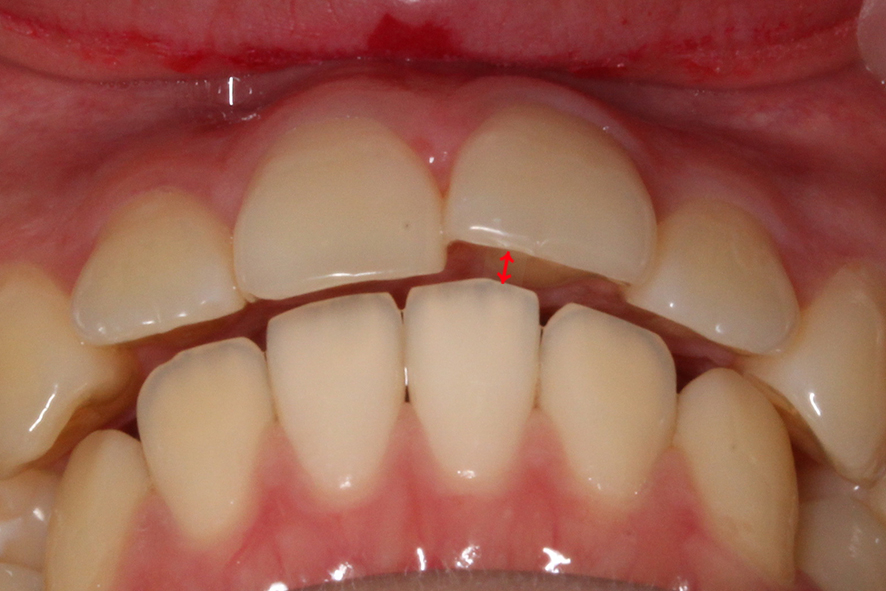

overjet 사진을 보면 돌출감이 심해 보이지

않았던 정면 및 overbite 사진과 달리

상악의 뻐드러짐이 심한 모습인데요,

구치부 교합을 확인해봐야 알겠지만

상악이 과하게 발달한 2급 부정교합

증상이 있을 것으로 보입니다.

이러한 전치부 교합 상태를 가진 분들의 경우

상하악 앞니가 서로 맞닿지 않기 때문에

아래 앞니에 의해 윗니의 설측면이

손상될 가능성이 있습니다.

또한 음식을 드실 때 치아의 절단력을

사용하기 어렵기 때문에 혀를 내밀어

절단하는 경우가 있는데요,

이러한 습관이 지속된다면

치아의 돌출이 더 악화될 가능성이 있습니다.